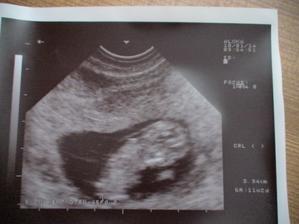

4.1.2010 KO 9tt+2 v pořádku, máme CRL 2,35cm, srdíčko tluče, mimísek si pěkně plaval.

14.1.2010 utz 10tt+5 máme CRL 3,94cm, všechno v pořádku, je to báječný pocit.